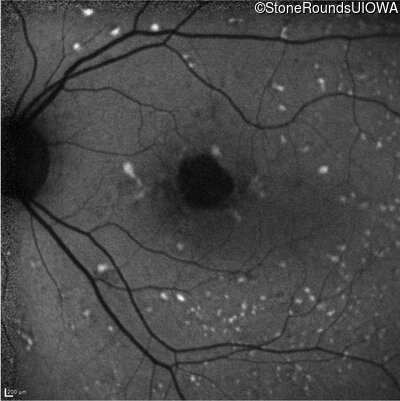

Infrared Fundus Photograph - Right - 20/20

Exemplar

Infrared Fundus Photograph - Left - 20/40 +1